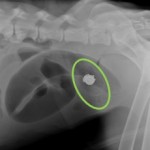

Cannon, a 5-year-old male Saint Bernard, came to Reber Ranch Veterinary Hospital because he was not acting like the sweet, gentle giant he normally is-in fact, we would soon find out that he was very sick. Cannon’s mom and dad noticed that he wasn’t eating, and they brought him to us to find out what was wrong. After an exam and some x-rays, we found out that Cannon had eaten something that he shouldn’t have. After a day of fluid therapy and medications, the foreign object just wouldn’t pass and Cannon was taken to surgery. During surgery, a small stuffed animal (actually, it was a stuffed Saint Bernard toy!) was removed from Cannon’s intestines, and we are happy to report that he made a resounding, full recovery.

Intestinal blockages occur when dogs and cats eat things (foreign bodies) that won’t pass through their gastrointestinal tracts. These can be emergencies, because blood supply is quickly cut-off by the object, and the intestines can start to become necrotic, or dead. Not every foreign object will show up on x-rays; Cannon was lucky because the toy he ate contained metal components that showed up as bright white on his x-rays, so it was easy to tell that he had eaten something he shouldn’t have. Toys, chew bones, tennis balls, and so forth are normally very safe to give to dogs. However, if you have a dog or cat who likes to chew up and swallow things they shouldn’t, you may want to avoid purchasing and giving them altogether.